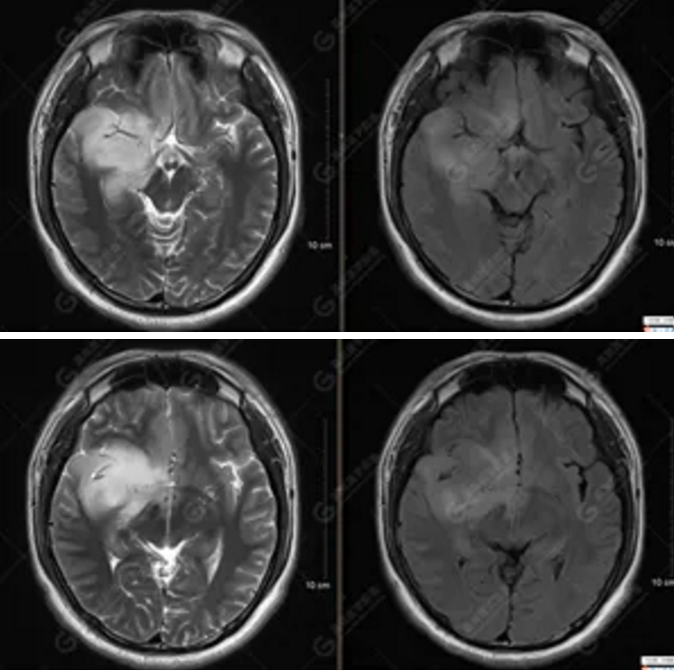

【MRI平掃及增強檢查所見】右側(cè)額顳島葉、右側(cè)海馬及右側(cè)基底節(jié)區(qū)見一團(tuán)塊狀異常信號影,累及右側(cè)下丘腦及視交叉,大小約5.1cm×4.5cm×4.3cm,呈長T1長T2信號,F(xiàn)LAIR序列呈等、稍高信號,DWI序列呈稍高信號,ADC圖高信號,增強后無明顯強化;病灶周圍見片狀長T1長T2水腫信號影,F(xiàn)LAIR序列呈高信號,病灶內(nèi)見右側(cè)大腦中動脈穿行。余腦實質(zhì)內(nèi)未見局灶性信號異常,增強后未見異常強化。右側(cè)側(cè)腦室輕度受壓,余腦室、腦池大小、形態(tài)均正常,中線結(jié)構(gòu)居中